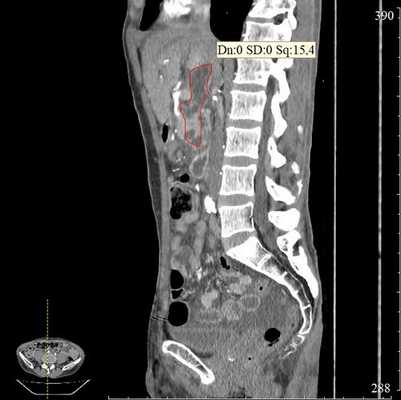

С помощью ультразвуковой навигации определяется безопасная траектория для внутреннего дренирования кисты. В инструментальный канал специального эхо-эндоскопа проводится цистотом, посредством которого формируется соустье между луковицей двенадцатиперстной кишки и просветом кисты (рис. 5 а, б).

Затем под контролем рентгеноскопии в полость кисты вводится струна-проводник для установки пластикового стента (double pigtail) диаметром 10 Fr и длиной 10 см. Осуществляется рентгенологический и ультразвуковой контроль: он подтвердил, что дистальный конец стента располагается в просвете кисты, проксимальный - в луковице двенадцатиперстной кишки (рис. 5 в, рис. 6). При эндоскопическом осмотре оценивается область сформированного соустья для исключения кровотечения (рис. 7).

Через 3 месяца после операции при контрольной КТ отмечена полная ликвидация кисты поджелудочной железы (рис. 8). В связи с этим стент, полностью выполнивший свою функцию, был удален.